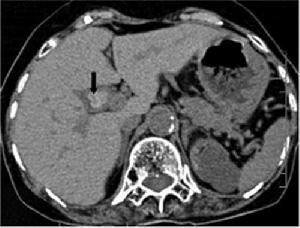

膽囊管綜合徵CT成像實驗室檢查:膽囊管綜合徵患者的血常規白細胞計數、分類及肝功能實驗基本正常。

(3)B型超聲、CT、MRI、X線膽囊造影等檢查未發現膽囊結石和占位性病變。當上述方法如仍不能作出診斷時,尚可採用以下方法協助診斷:①膽道放射測壓術加上膽道造影。②手術中將造影劑注入膽囊,並在放射線下追蹤造影劑到十二指腸的過程。通過此方法,容易確定阻塞的存在及其部位。